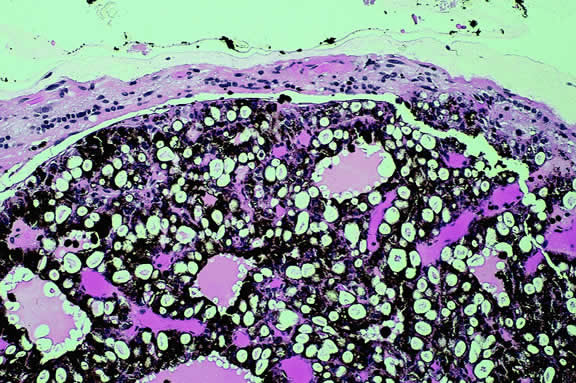

Choroidal melanomas produce abnormalities in the overlying retinal pigment epithelium including atrophy, hyperplasia, and the formation of drusen and drusenoid material.92 The overlying retina often shows photoreceptor loss and may develop cystoid edema. The latter tends to be more common in slower growing lesions, especially choroidal hemangiomas. After Bruch's membrane has ruptured, the vessels located in the mushrooming head of the tumor are often quite prominent, reflecting vascular stagnation caused by the compression at the waist of the tumor (see Fig. 22). Aggregates of macrophages that have ingested periodic acid-Schiff (PAS)-positive lipofuscin pigment and melanin from the damaged retinal pigment epithelium can be found in the subretinal fluid (Figs. 39 to 41). These are evident ophthalmoscopically as clumps of orange pigment that serve as a clinical marker for an actively growing neoplasm.80,81

Fig. 41. Orange pigment. Orange pigment is comprised of aggregates of macrophages that have phagocytized periodic acid-Schiff (PAS)-positive lipofuscin and melanin pigment released by retinal pigment epithelial cells that have been disrupted by the actively growing tumor. (Periodic acid-Schiff, × 100.)